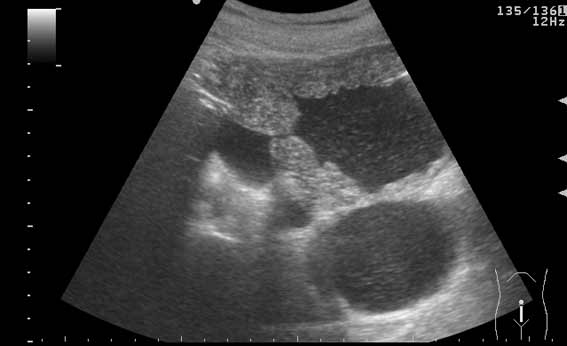

УЗИ мочевого пузыря у пожилого мужчины выявлены следующие изменения.

Signs of chronic urinary retention; evident thickening of the urinary bladder mucosa; large diverticulas. Residual volume evlaluation required; full prostatic assessment is recommended.

But really there are two ones on these pictures.

неравномерное утолщение стенок мочевого пузыря,признаки застоя в мочевом пузыре,расширенные дистальные отделы мочеточников,на первом снимке-дивертикул?слева,уввеличенная отечная простата

Все верно, за исключением того что простаты на картинках нет. Здорово, что Вы заметили расширение мочеточников. Есть также воздух в МП после цистоскопии.